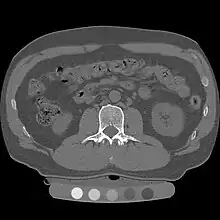

Quantitative computed tomography (QCT) is a medical technique that measures bone mineral density (BMD) using a standard X-ray computed tomography (CT) scanner with a calibration standard to convert Hounsfield units (HU) of the CT image to bone mineral density values.[1] Quantitative CT scans are primarily used to evaluate bone mineral density at the lumbar spine and hip.

In general, solid phantoms placed in a pad under the patient during CT image acquisition are used for calibration. These phantoms contain materials that represent a number of different equivalent bone mineral densities. Usually either calcium hydroxyapatite (CaHAP) or potassium phosphate (K2HPO4) are used as the reference standard.[2]

Originally, conventional 2D QCT used individual, thick CT slice images through each of multiple vertebrae which involved tilting the CT scanner gantry to align the slice with each vertebra. Today, modern 3D QCT uses the ability of CT scanners to rapidly acquire multiple slices to construct three-dimensional images of the human body. Using 3D imaging substantially reduced image acquisition time, improved reproducibility and enabled QCT bone density analysis of the hip.[1]